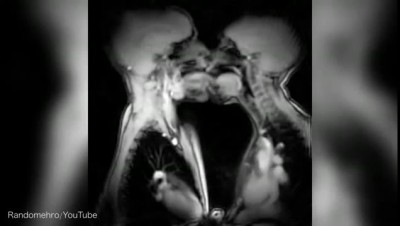

Просмотр файла «MRI scans take a look at internal organs during sex» ↓